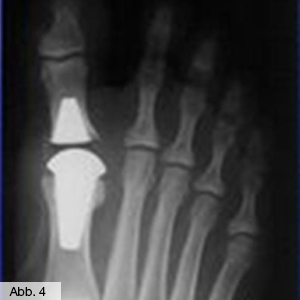

Arthrose des Zehengelenks

Wie auch bei den großen Gelenken führt der Verschleiß des Großzehengrundgelenks (Abb. 3) zu Bewegungs- und Belastungsschmerzen. Da dieses Gelenk für einen normalen Abrollvorgang beim Gehen äußerst wichtig ist, kann eine Arthrose sehr behindernd sein. Wenn eine Ruhigstellung des Gelenks durch Einlagen nicht mehr ausreicht, können hier operative Eingriffe helfen. Die Behandlungsspanne reicht von dem einfachen Abtragen störender Knochenzacken (Cheilektomie) über Knorpelplastiken bis zum Einsatz eines künstlichen Großzehengrundgelenks (Abb. 4) oder einer Versteifung.